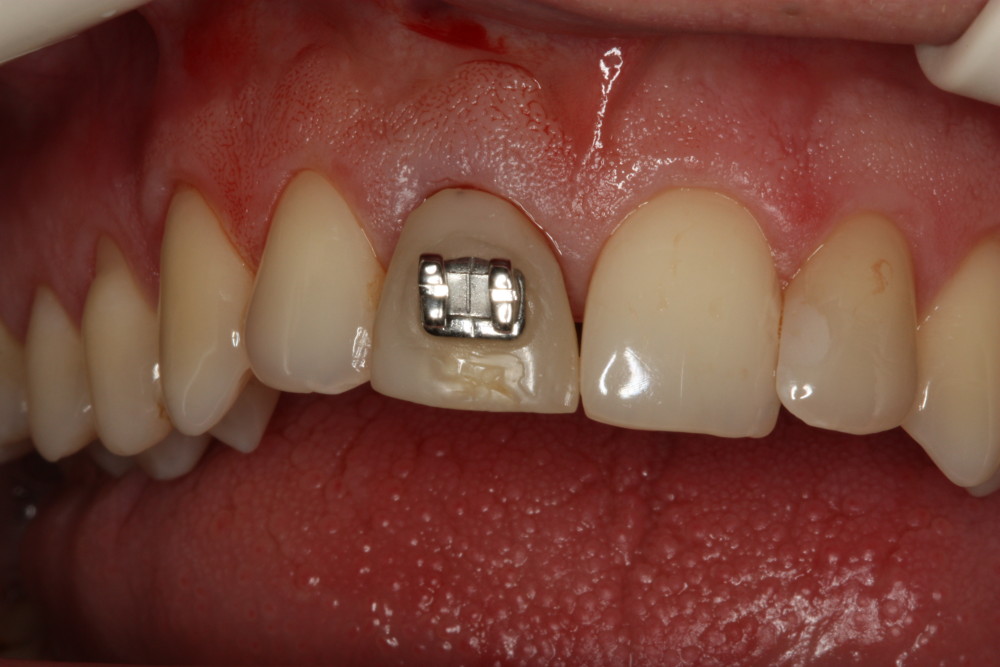

Przykład ekstruzji ortodontycznej za pomocą płytki termoformowalnej i zameczka ortodontycznego: